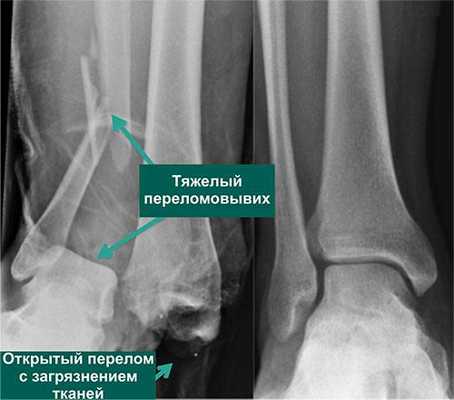

Далее пациент отправляется на рентгенографическое обследование. Снимок нужно делать в двух проекциях. Диагностировать разрыв связок на рентгене можно только, если речь идет о третьей степени патологии. Если картина нечеткая, ортопед может назначить рентген под нагрузкой или артрографию для понимания состояния суставной капсулы.

По статистике, 54% переломов и переломо-вывихов голеностопного сустава случаются в молодом возрасте, когда человеку важно сохранять трудоспособность. Эти травмы относятся к тяжелым повреждениям опорно-двигательного аппарата. Даже при качественном лечении они приводят к инвалидности в 3-12% случаев. Поэтому восстановление функций голеностопного сустава требует тщательного подхода, индивидуального для каждого пациента.